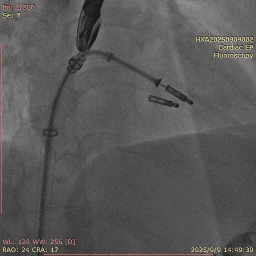

TEER手术时,有时候第一个夹子释放后因为腱索缠绕或者夹合不均匀导致夹子出现歪斜,这种歪斜可能导致瓣叶受力不均匀导致瓣叶损伤或者夹子脱落,若能纠正理论上会更好。这种情况下,可以使用第二个夹子的输送杆的将第一个夹子捋直,然后肩并肩植入第二个夹子进行纠正。操作时第二个夹子到达心室后需要先反转夹子,然后输送杆逐步靠近第一个夹子,不能用靠得太近使得夹子被挤压平移导致第一个夹子脱落,然后正转关闭夹子进行捕获夹合(图11-15)。

图12. P2大脱垂病例植入第一个夹子后出现夹子歪斜晃动大

图13. 第二个夹子关闭时可将第一个夹子卡入

图14. 反转夹子用输送杆将第一个夹子捋直

图15. 最后结果,双夹比翼双飞